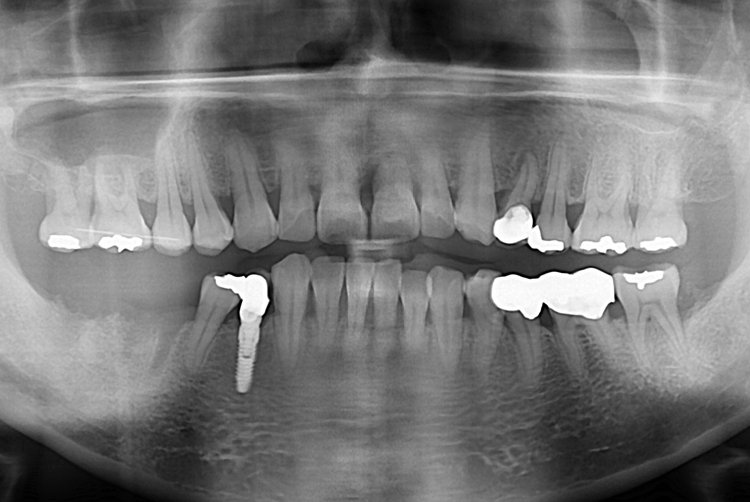

[임플란트] 어금니 임플란트

치료후 : 2017-09-29

세종치과는 많은 환자와 다양한 케이스를 바탕으로

항상 편안한 임플란트 수술을 제공하고자 노력하고,

오래동안 튼튼히 쓸 수 있는 임플란트 수술을 가장 큰 목표로 삼고 있습니다.